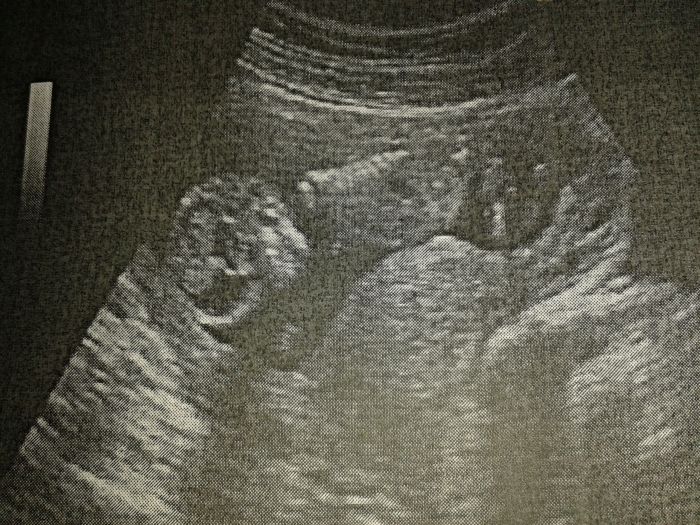

Míšo, holky mají pravdu, 1:94 je relativně Dobrý výsledek, to je skoro 1%, což je mnohem nižší, než možnost potratu. Zítra uvidíš v poradně. Ivy, jak jsi dopadla Ty? Tobě Dášo přeji také výborné výsledky. Posílám foto malého karatisty :-D

Ahojky, tak screening dopadl dobře, šíjové projasnění 1,3mm a z 80% to vypadá na holčičku. Podle MS jsem 13+5 podle utz 13:+3